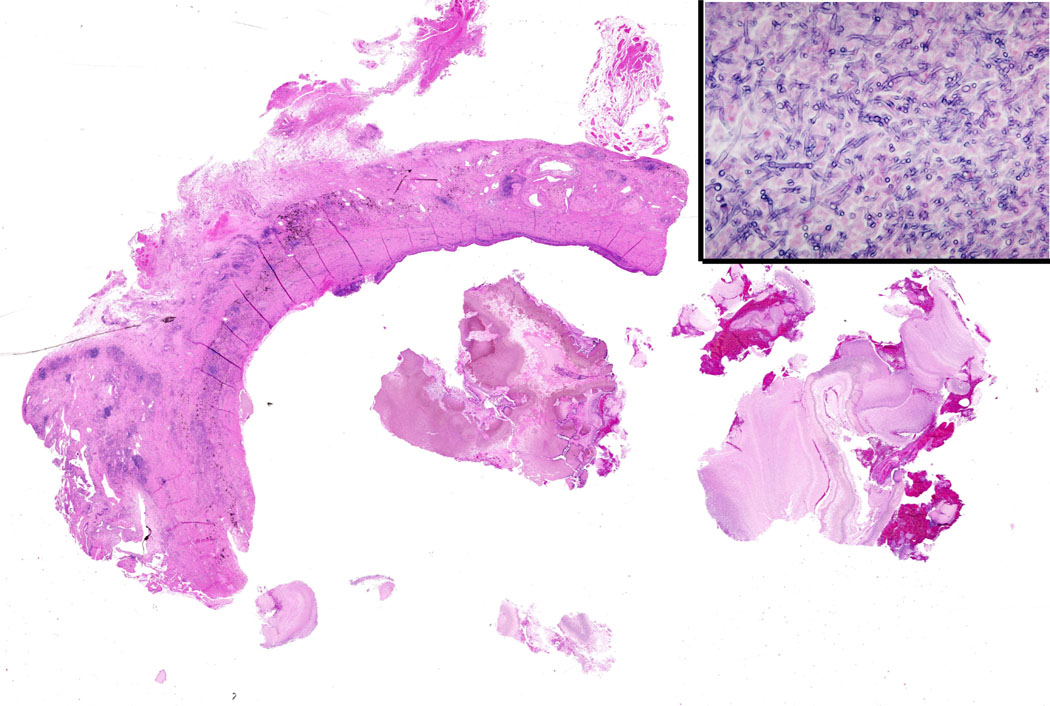

A standard lobectomy is performed. Dissection in the fissure is avoided as this will only lead to prolonged postoperative air leak. Instead, once the arterial anatomy has been defined, the fissures are completed with a stapling device. In rare instances the pulmonary parenchymal tissue is too thick to staple; in those cases, it must be taken with a clamp, cut, and then over sewn with chromic suture. A resected specimen is shown in Figure 5 along with the micrograph showing the typical appearance of recovered fungal elements (Figure 6).

| Figure 5: A resected specimen | Figure 6: Appearance of recovered fungal elements |